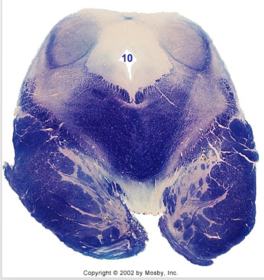

| Nucleus gracilis | |

| Nucleus cuneatus | |

| Fasciculus gracilis | |

| Fasciculus cuneatus | |

| Internal acruate fibers | |

| Lateral (external/accessory) cuneate nucleus | |

| Medullary pyramids | |

| Hypoglossal nucleus | |

| Hypoglossal nerve | |

| Dorsal motor nucleus of X | |

| Nucleus ambiguus | |

| Solitary tract | |

| Solitary nucleus | |

| ALS | |

| Medial lemniscus | |

| Medial longitudinal fasciculus | |

| Spinal tract of V | |

| Spinal nucleus of V | |

| Lateral (external, accessory) cuneate nucleus | |